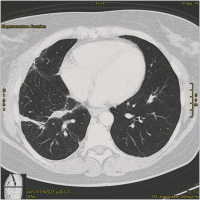

CT

Abbildung 2: CT mit Rundherd im rechten Lungenoberlappen.